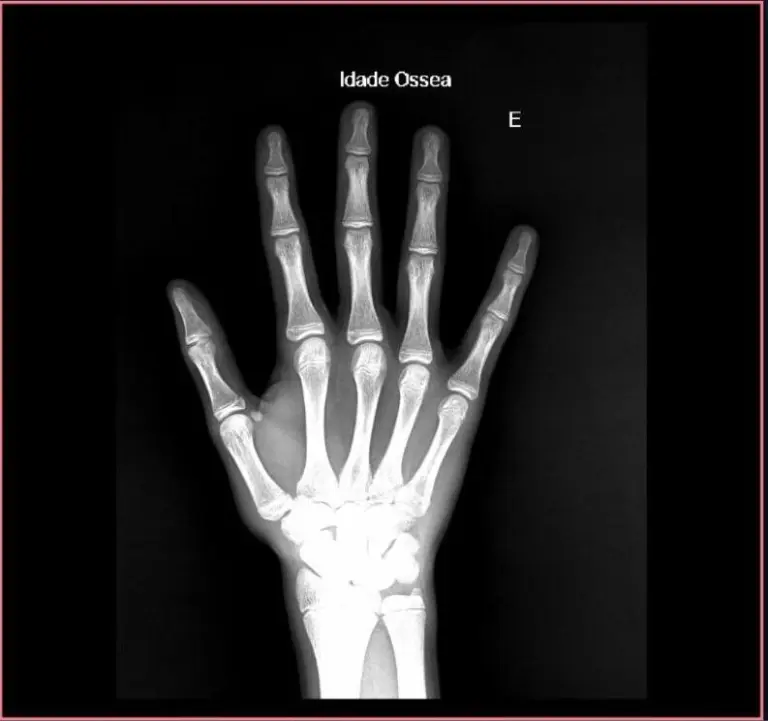

AI for Bone Age Calculation in Hand and Wrist X-Rays

Tools with this focus are capable of estimating an individual’s bone maturity based on the dimensions shown in the hand and wrist X-ray image.

Bone age analysis is especially relevant in areas related to pediatrics. In this case, the calculation algorithm is most relevant as a support basis for the diagnosis of the responsible physician.